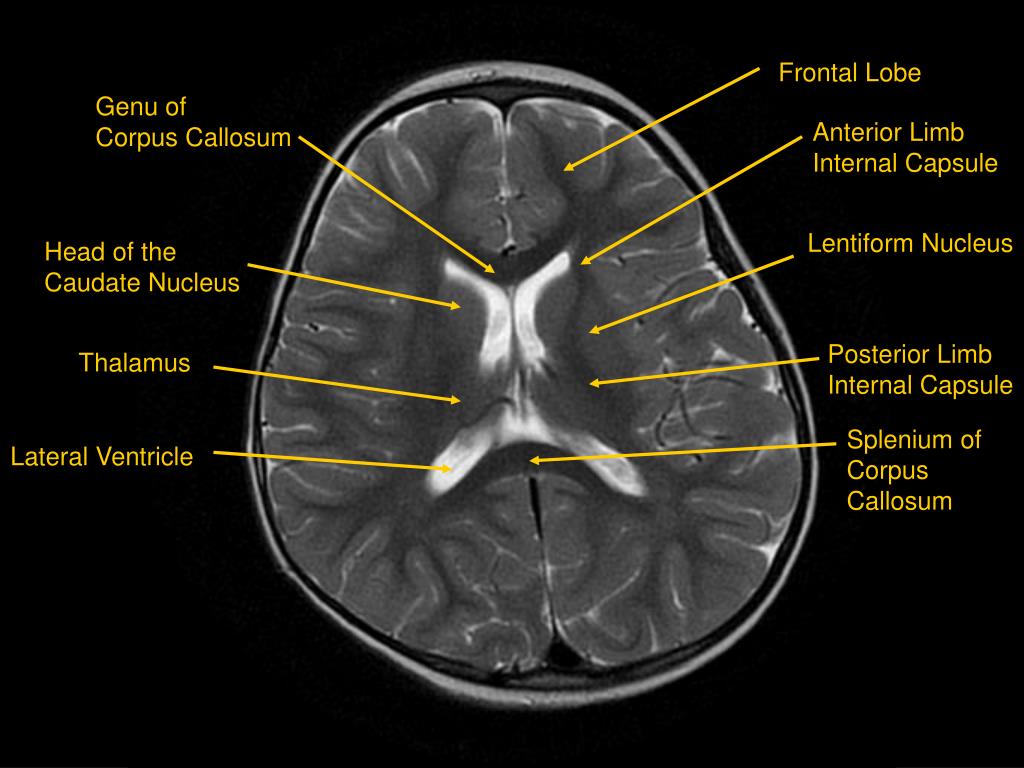

Brain Ventricles Labeled Mri . The third ventricle is located between the thalami and below the fornix of the brain. There are four such hollow spaces in the brain that house cerebrospinal fluid (csf): Two lateral ventricles, a third ventricle and a fourth ventricle. The ventricular system in the brain is a series of interconnecting spaces and channels within the brain composed of cerebrospinal fluid. The cerebral ventricular anatomy is labeled. Note, however, that mcrae’s line (basion to the.

The third ventricle is located between the thalami and below the fornix of the brain. The cerebral ventricular anatomy is labeled. Note, however, that mcrae’s line (basion to the. There are four such hollow spaces in the brain that house cerebrospinal fluid (csf): The ventricular system in the brain is a series of interconnecting spaces and channels within the brain composed of cerebrospinal fluid. Two lateral ventricles, a third ventricle and a fourth ventricle.